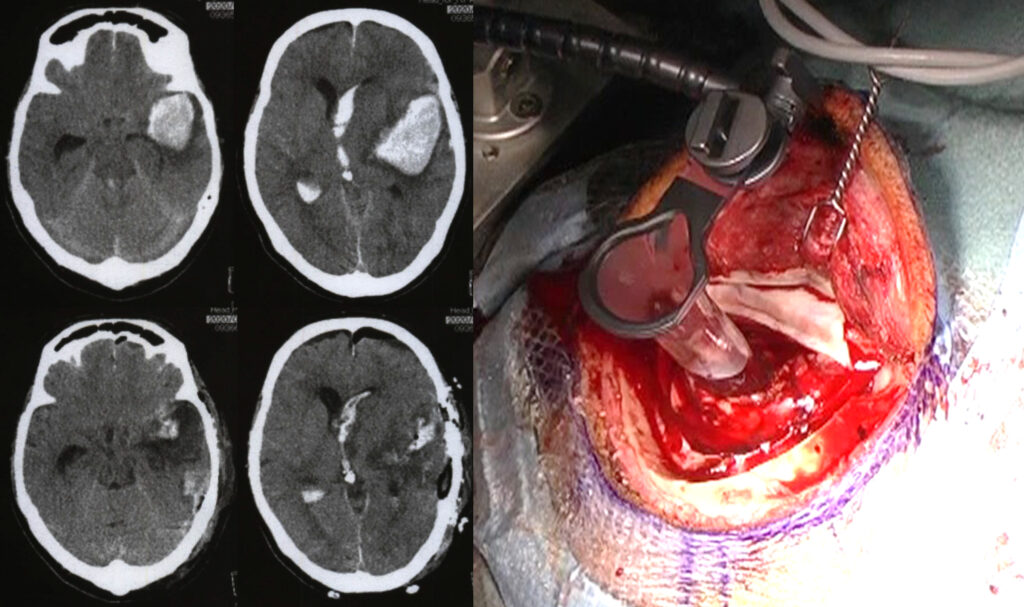

小さな脳内出血は、血圧管理を中心とする内科的治療で回復しますが、大きな脳出血は、急性期に血腫を除去して脳に対する圧迫を解除するほうが、良好な回復につながる場合があります。

その際、小さな開頭で内視鏡下に脳内血腫を除去する方法があります。近年、内視鏡下に脳内血腫を除去する手技が確立してきました。手術時間も短く、身体への負担も少なく、効果的に脳内血腫を除去できます。